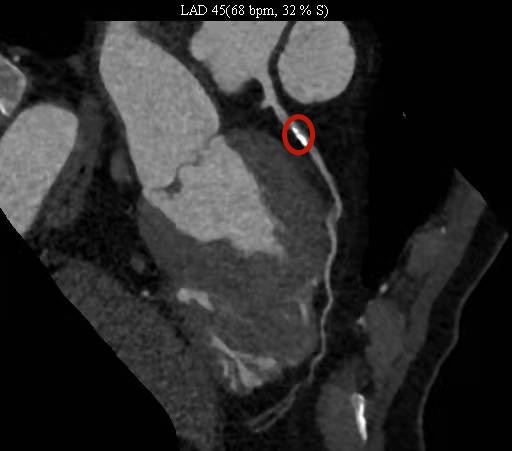

冠脉CT是利用CT快速多层扫描和图象重建技术,对患者的冠状动脉进行检查的方法。

冠脉CT检查快速无创,不需要注射造影剂就可以得到较清晰的冠状动脉图象,医生可以对冠脉病变部位及狭窄程度进行初步了解。

如果发现有严重的冠状动脉狭窄,则需要进一步行冠状动脉造影检查。这是明确冠状动脉疾病及严重程度的“金标准”,但它是一个有创伤的检查,需要将导管经大腿股动脉或其它周围动脉送至主动脉,通过碘对比剂的注入使冠状动脉显影,将冠状动脉阻塞的位置、程度与范围更为清晰明确地显现出来。

冠脉CT示钙化斑块导致管腔狭窄(红圈处)